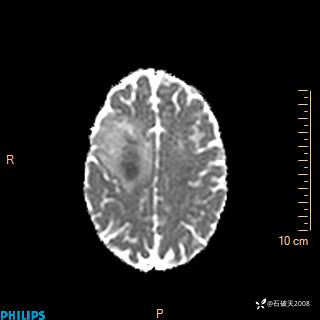

2024.2.21MR

增强轴位